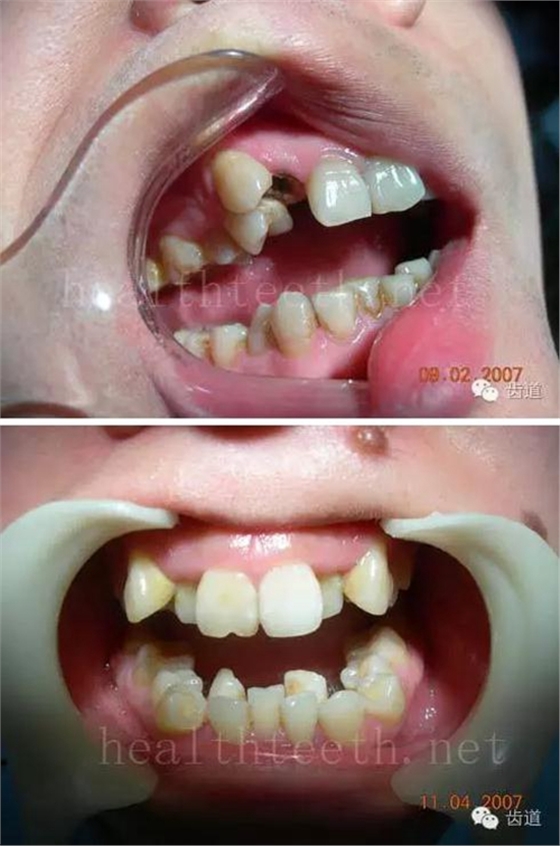

12歲孩子門牙的齲齒

18歲孩子的口腔狀況